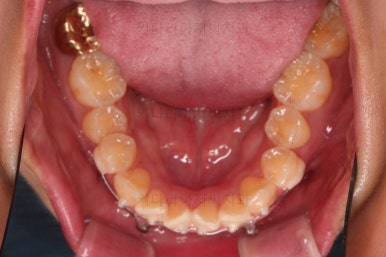

1. 초진

초진 시 입안의 모습입니다.

어금니 쪽은 약간 삐뚤긴 하지만 꼭 교정해야 할 정도는 아니고, 불편감 없이 비교적 잘 맞물리는 상태였습니다.

다만, 앞니ㅉㄱ이 공간이 부족해서 중간 치아들이 많이 회전되어있는데, 이를 환자분들의 표현에 따르면 "나비치아" 라고 부릅니다.

위아래 중간 앞니가 모두 나비치아처럼 되어있고요.

윗니가 아랫니보다 앞쪽으로 나와 있는 모습에 아래앞니가 윗니쪽으로 깊숙이 올라간 "과개교합" 양상을 보였습니다.